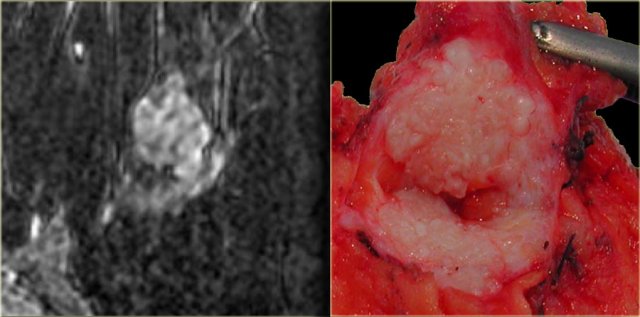

On the left an example of a classic fibroadenoma: a round, smoothly marginated lesion

with some black or gray areas on the inside, which are the non-enhancing septations.

This lesion has a type 1 curve.

On the far left is another example of a fibroadenoma with clear non-enhancing septations. These septations are also visible on the gross pathology.